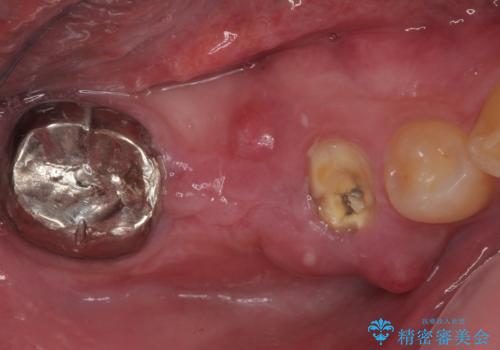

- むし歯を放置したことで、歯茎で膿が腫れ上がったしまったとのことで来院された患者様です。

ブリッジの支台歯が痛みを覚え、近医でブリッジを切断してもらって以降、そのままにしてしまったとのことでした。

問題が起きていた手前の歯から膿が出てきたことを自覚して当院を来院されましたが、既に歯根破折をしており、抜歯が必要な状態でした。

咬合力が非常に強い患者様であり、2歯欠損のブリッジ(しかも大臼歯は失活歯)は歯根破折のリスクが高すぎると判断し、抜歯部および欠損部に対して、インプラントによる補綴治療を行うこととしました。